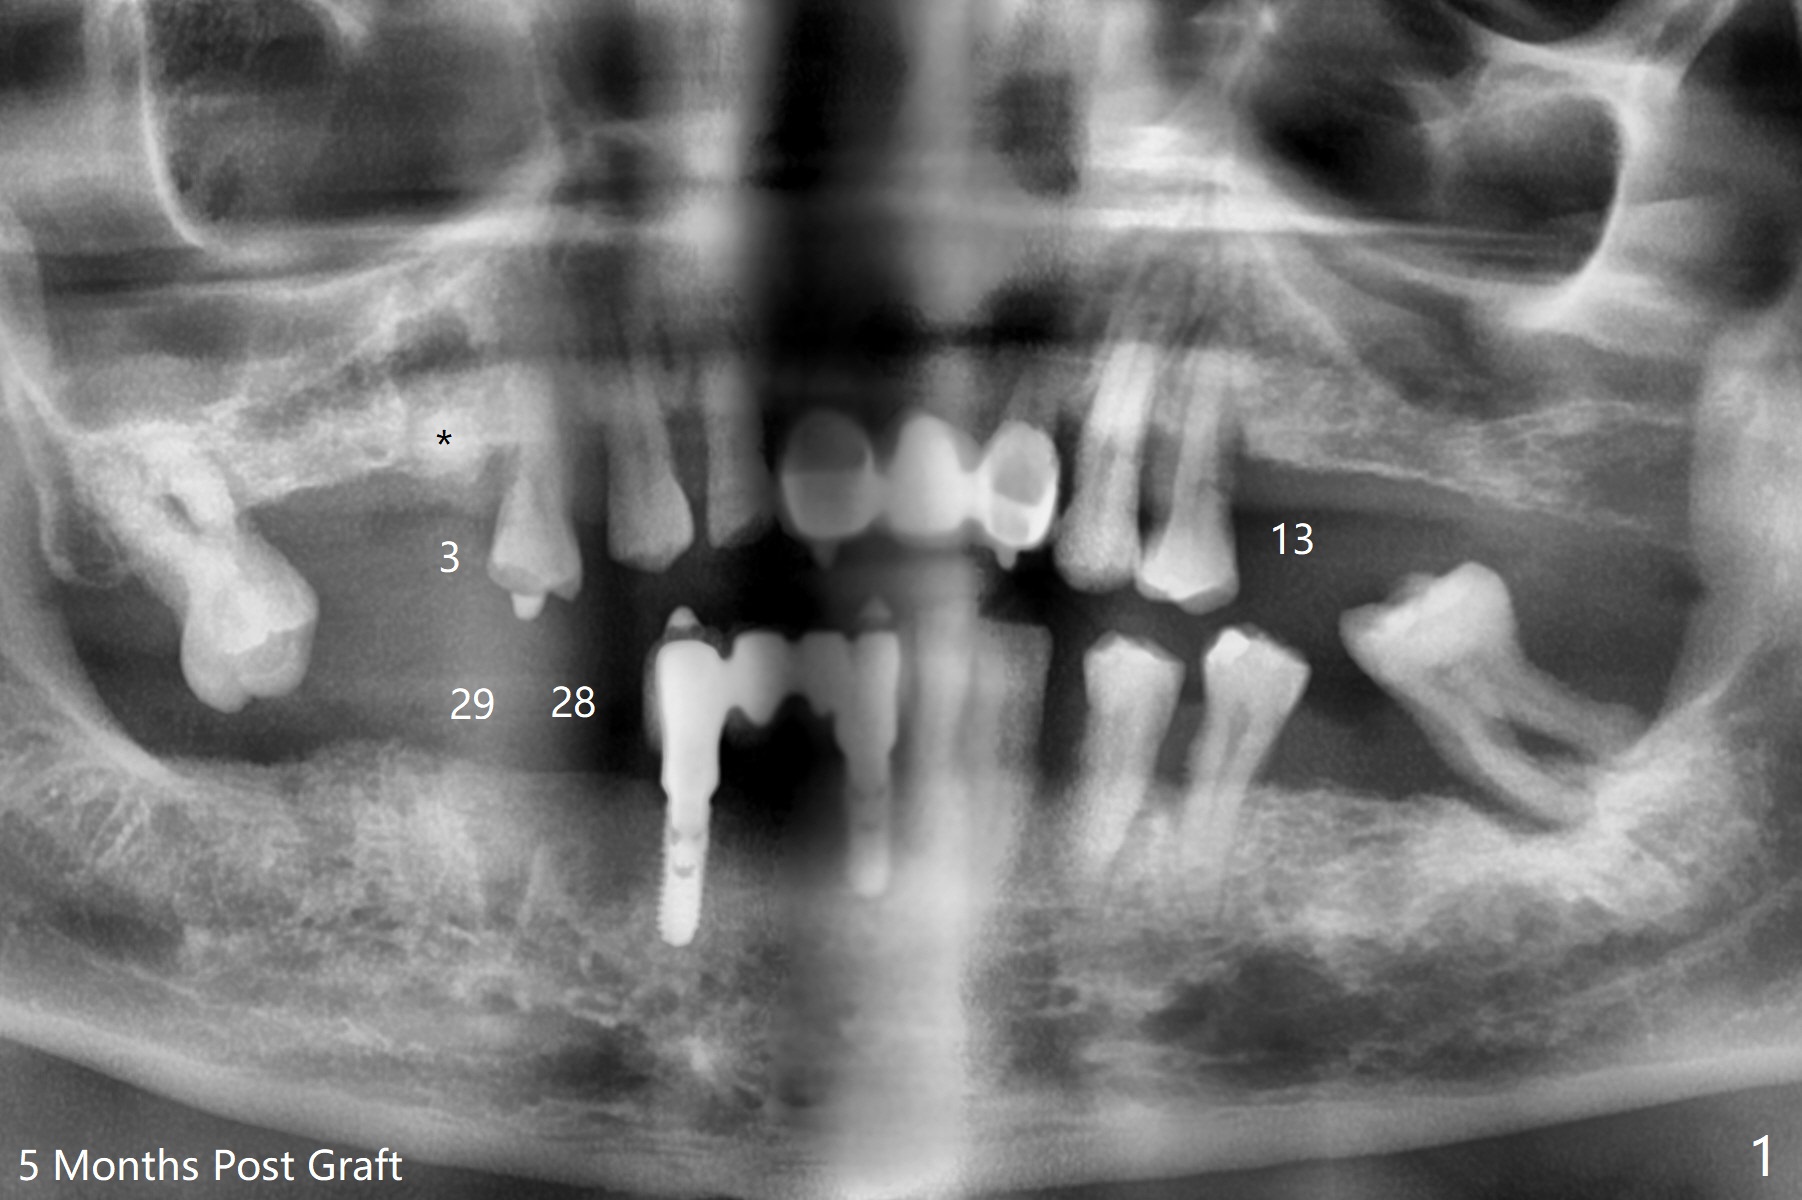

54岁男,28,29植骨后5个月,回来要求3,13,28,29种植(图一)。3号牙需要切开除去残根(图二:*),然后导板种植,准备两个PRF膜。为了保证植牙间距离,尝试在28,29处植入3.5x13毫米植体(图三,四)。在13号牙种植时(图五),考虑12号牙腭侧植骨(图六)。为了减少对12号牙咬合创伤,考虑4个植牙即刻修复。